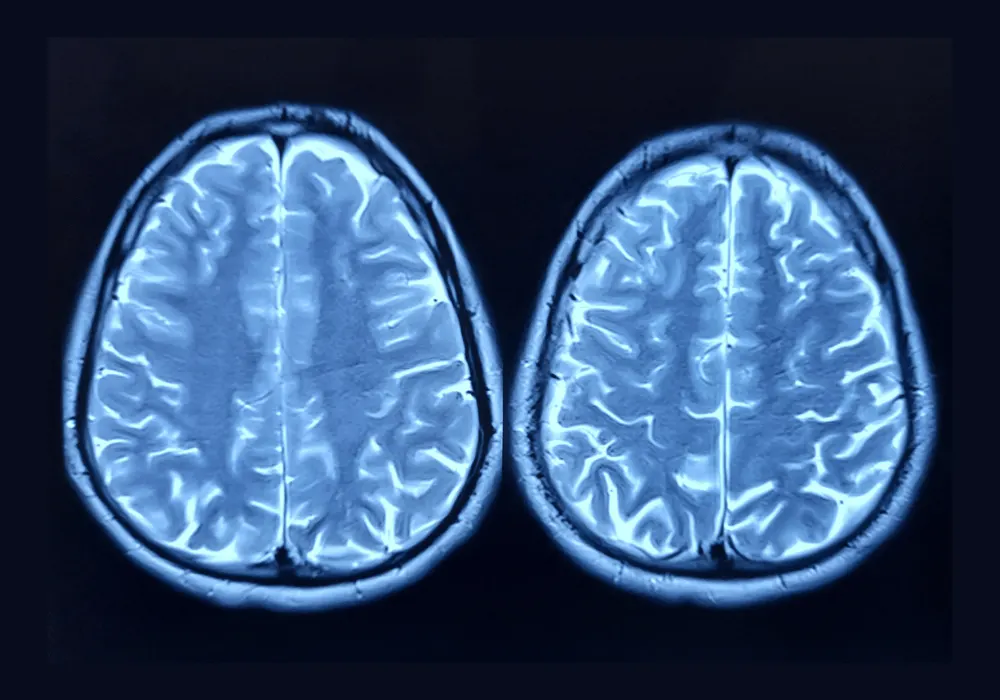

The rapid advancement of large language models (LLMs) has led to increasing interest in their application within medical diagnostics. While traditional text-based models have demonstrated potential in clinical decision-making, newer multimodal models such as OpenAI’s GPT-4 with vision (GPT-4V) introduce the capability to process both textual and imaging data. This evolution raises expectations for improved diagnostic performance in radiology, where accurate interpretation of medical imaging is crucial. However, studies have indicated that the effectiveness of these models depends significantly on how input data is structured and presented. A recent study published in Radiology explored the impact of different multimodal prompt configurations on the accuracy of GPT-4V in diagnosing complex brain MRI cases. The findings highlight the importance of specific prompt elements, particularly textual descriptions of imaging findings, in enhancing the model’s diagnostic accuracy. Understanding these insights is key to optimising AI-assisted radiology and ensuring its reliable application in clinical settings.

GPT-4V’s capability to analyse both images and text suggests that integrating multimodal inputs should enhance diagnostic accuracy. However, the study found that merely providing images—whether unmodified or annotated—resulted in extremely poor performance, with diagnostic accuracy as low as 2.2%. This suggests that, unlike human radiologists, who possess an innate ability to interpret visual patterns and detect abnormalities, LLMs require additional context to generate meaningful diagnostic insights. The inclusion of a patient’s medical history provided some improvement, as it allowed the model to establish a clinical framework for its analysis. However, the greatest impact on diagnostic performance was observed when detailed textual descriptions of radiologic findings were included in the prompt. This finding highlights a fundamental limitation of LLMs in medical imaging analysis: they do not yet possess the ability to independently extract detailed pathological features from images with the accuracy and nuance required for differential diagnosis. Instead, they rely heavily on structured textual inputs to bridge the gap between raw visual data and their text-based reasoning processes.

The study evaluated seven distinct prompt configurations, each incorporating different combinations of four key elements: unmodified images, annotated images, medical history and textual image descriptions. The results demonstrated that the highest diagnostic accuracy (69%) was achieved when all four elements were provided as input. Notably, prompts that included an image description—whether combined with medical history or presented alone—consistently outperformed those that relied solely on visual data. The presence of a medical history contributed to a moderate increase in accuracy, but textual descriptions of imaging findings proved to be the single most influential factor.

Regression analysis confirmed this observation, showing that image descriptions had the strongest positive impact on diagnostic accuracy, followed by medical history, while image annotations provided no significant improvement. In contrast, providing only images—either unannotated or with annotations—resulted in very low accuracy, reinforcing the idea that GPT-4V lacks the capability to independently interpret medical imaging at a high level. These findings suggest that structuring prompts effectively is crucial for maximising the model’s ability to process and contextualise radiologic data. They also imply that even in an AI-assisted diagnostic setting, the role of expert radiologists remains essential in generating high-quality input data.